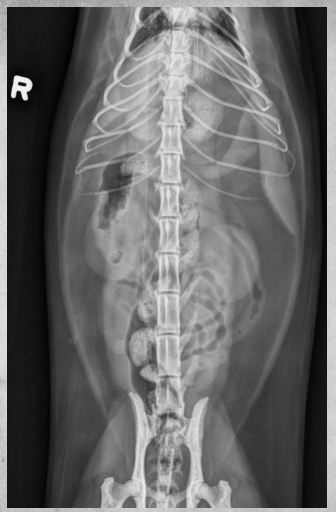

●9 yo mixed breed female dog

(sterilized)

●Increased ALP

● Impressive amount of subcutaneous and intra-abdominal fat.

● Enlarged liver – changed gastric axis pushed caudally, rounded edges, extending past the costal arch.

● At least two round soft tissue opacity structures superimposed on ventral liver (lateral view).

● Round soft tissue structure cranial to right kidney.

● Mass in adrenal gland or pancreas

● Hepatic nodules (benign vs metastatic disease)

SI gas is normal because bowels empty.